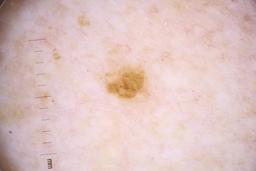

- Name: Challenge 2020: Training

- Number of images: 33,126

- Number of specified lesions: 32,701

- Number of specified patients: 2,056